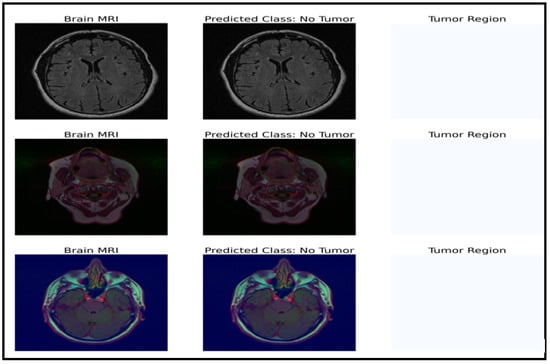

The model can be used for brain tumor segmentation. The result of the U-Net architecture is a probability map representing the likelihood of each pixel in the input image belonging to the tumor region. A threshold can be set on this map to obtain the binary segmentation map, which indicates the presence or absence of the tumor in each pixel of the input image. The binary segmentation map obtained from the U-Net can be used to improve the accuracy of the brain tumor detection and classification tasks performed by the CNN model with fine-tuned ResNet50. For example, the binary segmentation map can focus the proposed model’s attention on the tumor region, reducing false positives and improving the overall accuracy. To integrate the outputs from the CNN model with fine-tuned ResNet50 and the U-Net architecture, the binary segmentation map can be overlaid onto the input MRI image to highlight the tumor region. Figure 7 shows the segmentation results for a selected tumor region, while Figure 8 shows the results for a non-tumor region. This combined approach can provide valuable insights for clinical diagnosis and treatment planning.

Figure 8.

Dataset classification and model prediction of no-tumor regions.